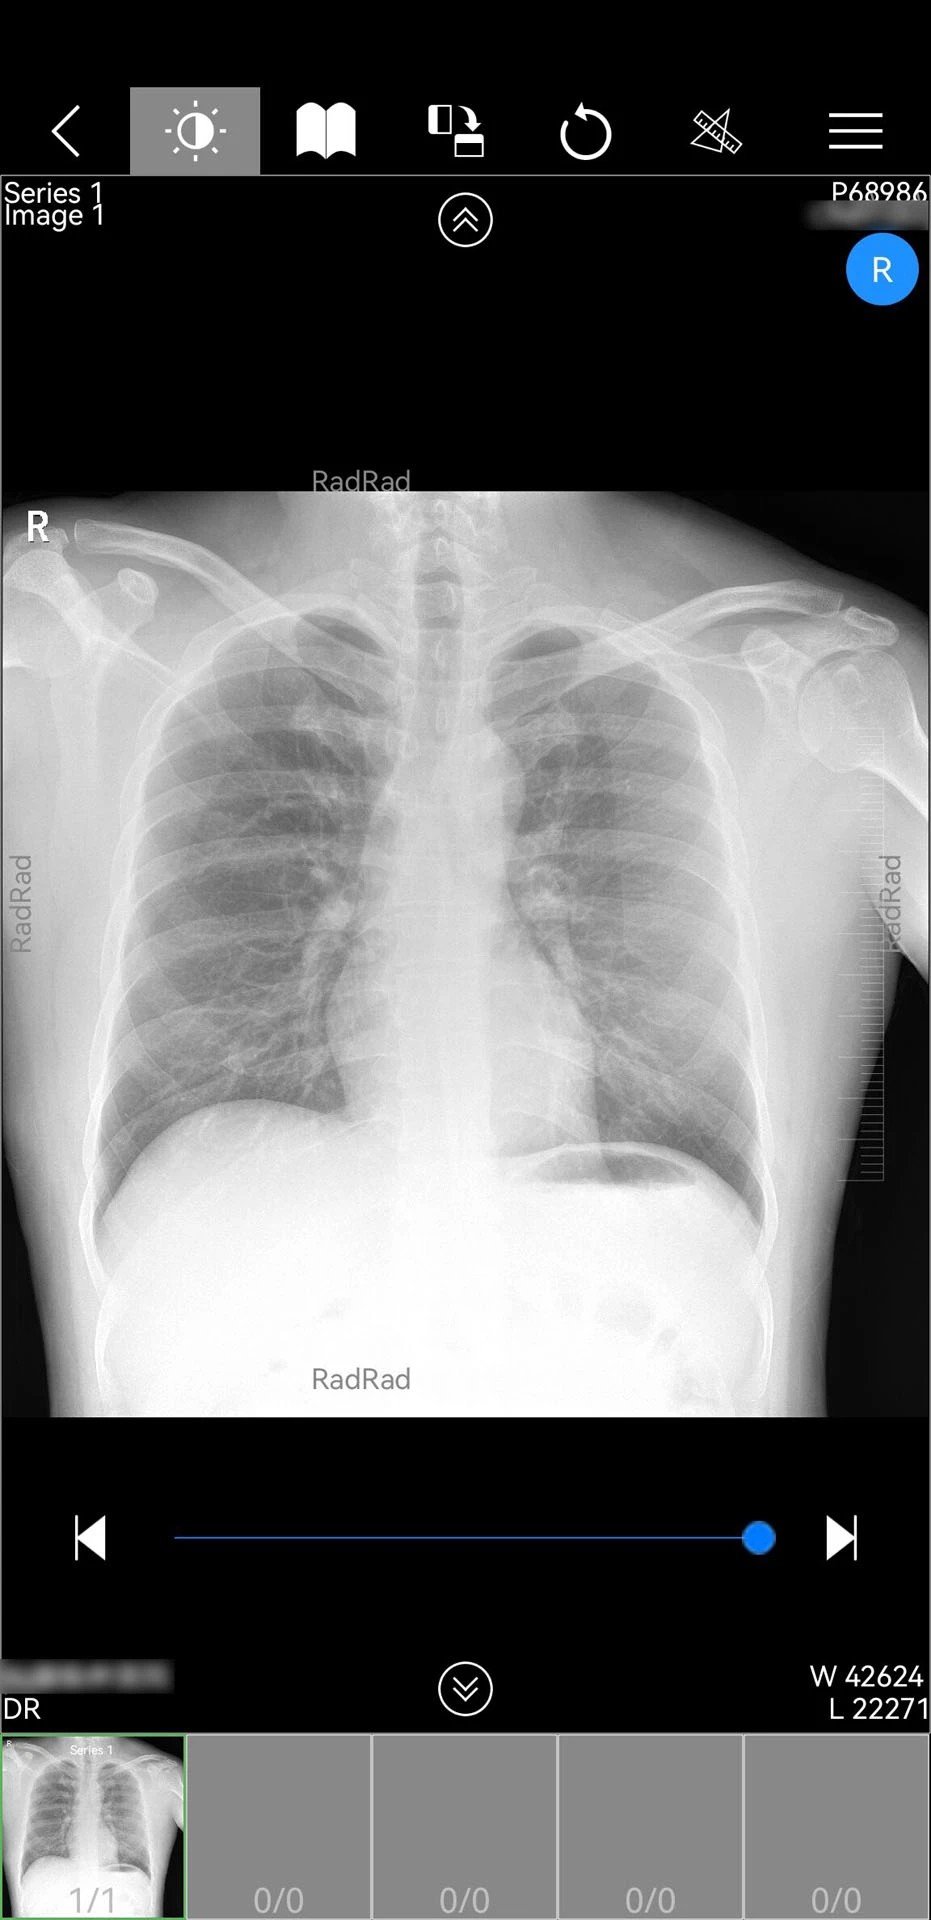

1. 多模态影像支持:支持DICOM格式影像的快速加载与多平面重建,医生可自由调整窗宽窗位、缩放旋转影像,并标注关键病灶区域,辅助精准诊断。例如,在肺癌筛查中,医生可通过三维重建功能直观观察肺部结节形态,结合AI辅助分析系统生成恶性概率评估报告。

3. AI辅助诊断:集成深度学习算法,可自动识别CT影像中的肺结节、骨折等常见病变,并标注位置、大小及恶性概率。例如,在胸部CT筛查中,AI系统可在3秒内完成全肺扫描,识别直径≥3mm的结节并生成结构化报告。